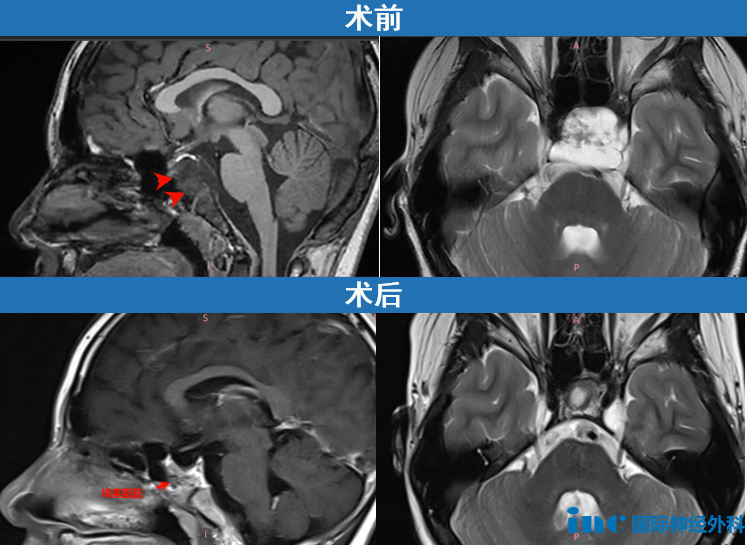

5年时间一晃而过。今年小海的头痛突然加重了,复查发现颅底斜坡区一个33×26×33mm的大肿瘤,已经侵袭左侧海绵窦,导致垂体移位,就连垂体柄都已被推歪。医生高度怀疑这是一个嵴索瘤。

症状加重,病灶又大,这一次小海不能再等了!当找到福教授,小海手术情况如何,点击阅读:天坛医院手术纪实|全切嵴索瘤后4个月,爱运动的他帅气归来!